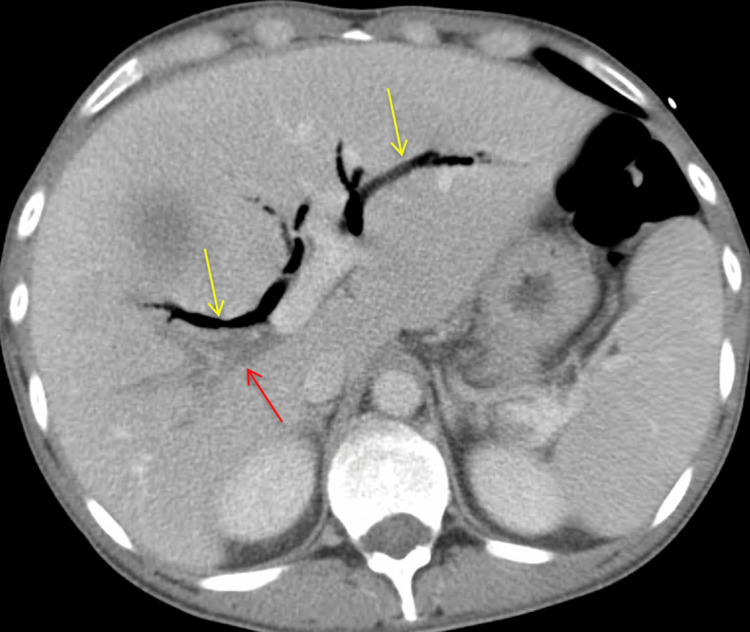

Post-procedure, the patient developed improved jaundice and abdominal pain and was able to tolerate a regular diet with discharge home on the fifth post-procedure day. He re-presented three weeks later due to progressive cramping abdominal right upper quadrant (RUQ) pain, nausea, and bilious emesis. An abdominal ultrasound and CT demonstrated a large 8.5 cm liver abscess in the right hepatic lobe, with a posterior defect in the hepatic margin of the gallbladder wall (Figures 4–6). There was noted septic thrombosis of the right portal venous system. He underwent emergent CT-guided percutaneous transhepatic drainage of the liver abscess, with cultures demonstrating Streptococcus anginosus. He was initiated on empiric IV piperacillin-tazobactam, followed by a transition to a four-week course of oral amoxicillin-clavulanate 875-125 mg twice daily after sensitivity results were completed. He was initiated on therapeutic enoxaparin followed by conversion to oral apixaban for a planned six-month course for portal thrombosis. Repeat CT imaging demonstrated stable portal thrombus without extension or enlarging hepatic abscess. He was discharged home with planned interval endobiliary stent removal and delayed interval cholecystectomy. No complications or recurrent symptoms were observed during the patient’s follow-up after discharge.